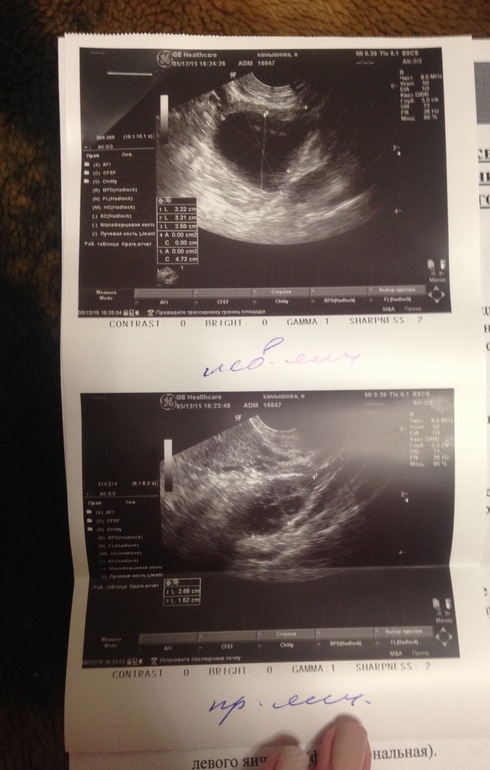

Киста+ тонкий эндометрий.

Во-первых, такие размеры в данный день цикла могут быть вполне присущи фолликулу. По определению киста- это образование более 3 см с диаметре. Естественное, если это образование сохраняется с прошлого цикла, то речь идет о кисте. Если же его видят в этом цикле впервые, еще и на 13 день, то я бы не рискнула говорить о кисте.

Тогда Вам следует пройти УЗИ после менструации, а еще лучше после предполагаемой овуляции, примерно на 20-22 день цикла. Так вы сможете и проверить, есть ли киста и оценить толщину эндометрия, что также полезно во время планирования

Чтобы убедиться что точно ли это киста, надо пройти УЗИ на 6-7 дц сразу после месячных..

Потому что размеры кисты от 30 мм и более.врач у вас плохой попался(

Катюшечка,а вот эндик подвел...тонковат.но вы все равно ща тест замочите и бегите к мужу скорей.дня через 3 на узи еще.там будет у вас отличное жт!

с 13 до 19 дц эндометрий дорастет до 9 точно, а 9 норма, для 2 фазы. Не знаю откуда такие реф пределы от 9 до 1,3, они для 2 фазы вобщето а у вас явно первая учитывая что О на 19 день. У меня просто также, на 13 дц был эндик около 7 мм, но О на 17-18 и он нарос до 9.